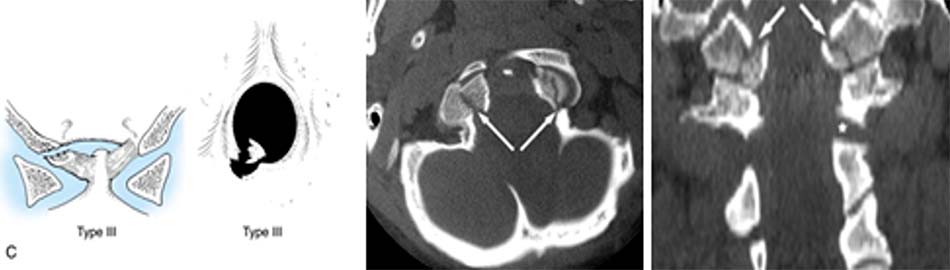

Dựa trên hình ảnh Xquang, cắt lớp vi tính và cơ chế tổn thương, Fielding chia trật C1-C2 thành 4 loại [42]:

- Loại 1: trật nhẹ diện khớp, ADI < 3mm.

- Loại 2: đứt dây chằng ngang, ADI: 3 – 5 mm.

Hình 1.28. Trật C1-C2 loại 1 và 2 - Loại 3: đứt dây chằng ngang, dây chằng cánh, ADI > 5mm.

- Loại 4: trật C1 ra sau so với C2, thường phối hợp gãy mỏm nha hoặc vỡ cung trước C1.

Hình 1.29. Trật C1-C2 loại 3 và 4